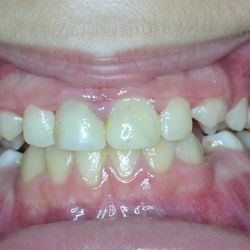

Η νεαρή αυτή ασθενής προσήλθε στο ιατρείο παραπονούμενη για την εμφάνιση των τεσσάρων άνω τομέων της.

Τα δόντια είχαν με την πάροδο των ετών σπάσει στην κοπτική τους επιφάνεια και το φαινόμενο αυτό επιδεινώνονταν σταδιακά με απώλεια όλο και περισσότερης οδοντικής ουσίας.

Αποφασίστηκε να αποκατασταθεί η δομική ακεραιότητα των δοντιών αυτών με χρήση σύνθετης ρητίνης νανουβριδικής τεχνολογίας (Herculite XVR Ultra/Kerr).

Η αποκατάσταση τους έγινε σε ένα ραντεβού και το αισθητικό αποτέλεσμα ικανοποίησε στο ακέραιο τις προσδοκίες της ασθενούς μας.